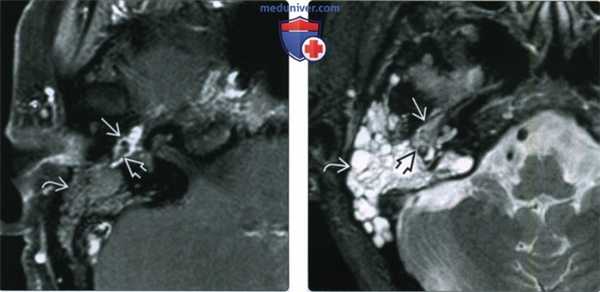

(Слева) При MPT Т2 ВИ в аксиальной проекции определяется крупное новообразование, исходящее из яремного отверстия; в ткани образования определяются множественные «пустоты потока» вследствие высокой скорости кровотока. Такая картина помогает дифференцировать эту опухоль от других новообразований этой зоны. Также наблюдается экссудация в ячейки пирамиды височной кости, вызванная обструкцией евстахиевой трубы.

(Справа) Корональная МРТ Т1ВИ FS с КУ: контрастная параганглиома яремного гломуса, прорастающая основание черепа и распространяющаяся кверху и латерально к среднему уху и наружному слуховому проходу. Этот пациент 15 лет с мутацией SDHB находится в группе высокого риска развития агрессивной параганглиомы.